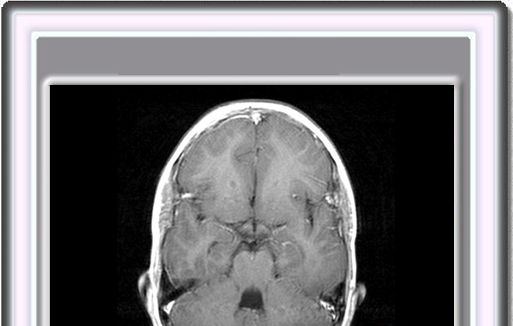

En las imágenes de RM en T1 se observan múltiples pequeños nódulos hiperintensos a lo largo del subepéndimo de las paredes ventriculares laterales. Estos nódulos son hipointensos en las imágenes en T2

Suelen en la región subcortical de ambos hemosferios cerebrales múltiples hipointensas lesiones en T1 que pasan a ser hiperintensas en T2